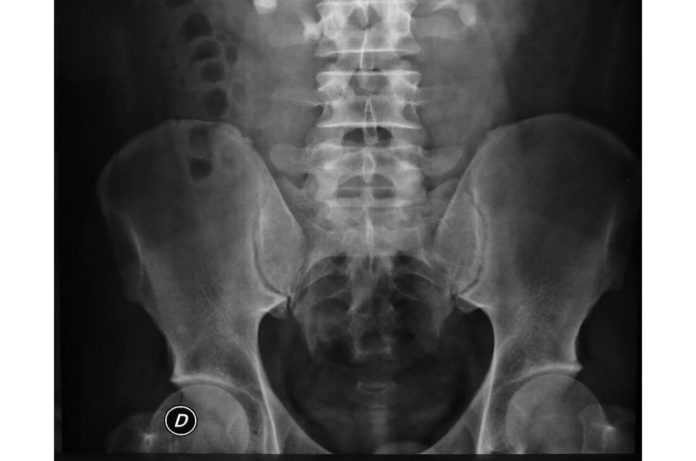

Esta articulación es la que hace de anclaje de la pelvis con la cabeza del fémur, que es el hueso más largo de nuestro cuerpo. La pelvis es una cavidad del hueso de la cadera que tiene forma de semiesfera y se denomina acetábulo. Aquí es donde se encaja la cabeza femoral o el extremo superior del fémur.

La cabeza femoral se mueve en el interior del acetábulo para permitirnos correr o andar. Ambos están recubiertos por una capa cartilaginosa que se encarga de facilitar el deslizamiento de ambas partes sin dolor. La cadera, finalmente, está rodeada de tejidos fibrosos y ligamentos que conforman la articulación y que nos permiten realizar movimientos como abducción, rotación interna o externa, aducción, flexión y extensión.